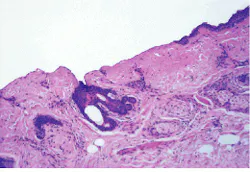

In addition, SEO says the erbium laser is not necessarily slower than the CO2 laser for resurfacing; it depends on fluence, spot size, and repetition rate. Thus, if an erbium laser has a repetition rate of 4-5 Hz, it has enough energy to remove the epidermis in one to two passes (see Fig. 2).Premier Laser Systems (Irvine, CA) has been conducting dermatological studies of its FDA-approved erbium laser for about a year. Although the company’s clinical work has shown that there is less pain and faster healing with the erbium than with the CO2 laser for resurfacing, Premier is delaying marketing its system until the FDA position on this application becomes clearer. Even so, last December Premier formed an alliance with Mattan Corporation (Calgary, Alberta, Canada), which owns and operates several cosmetic-surgery centers in the USA.